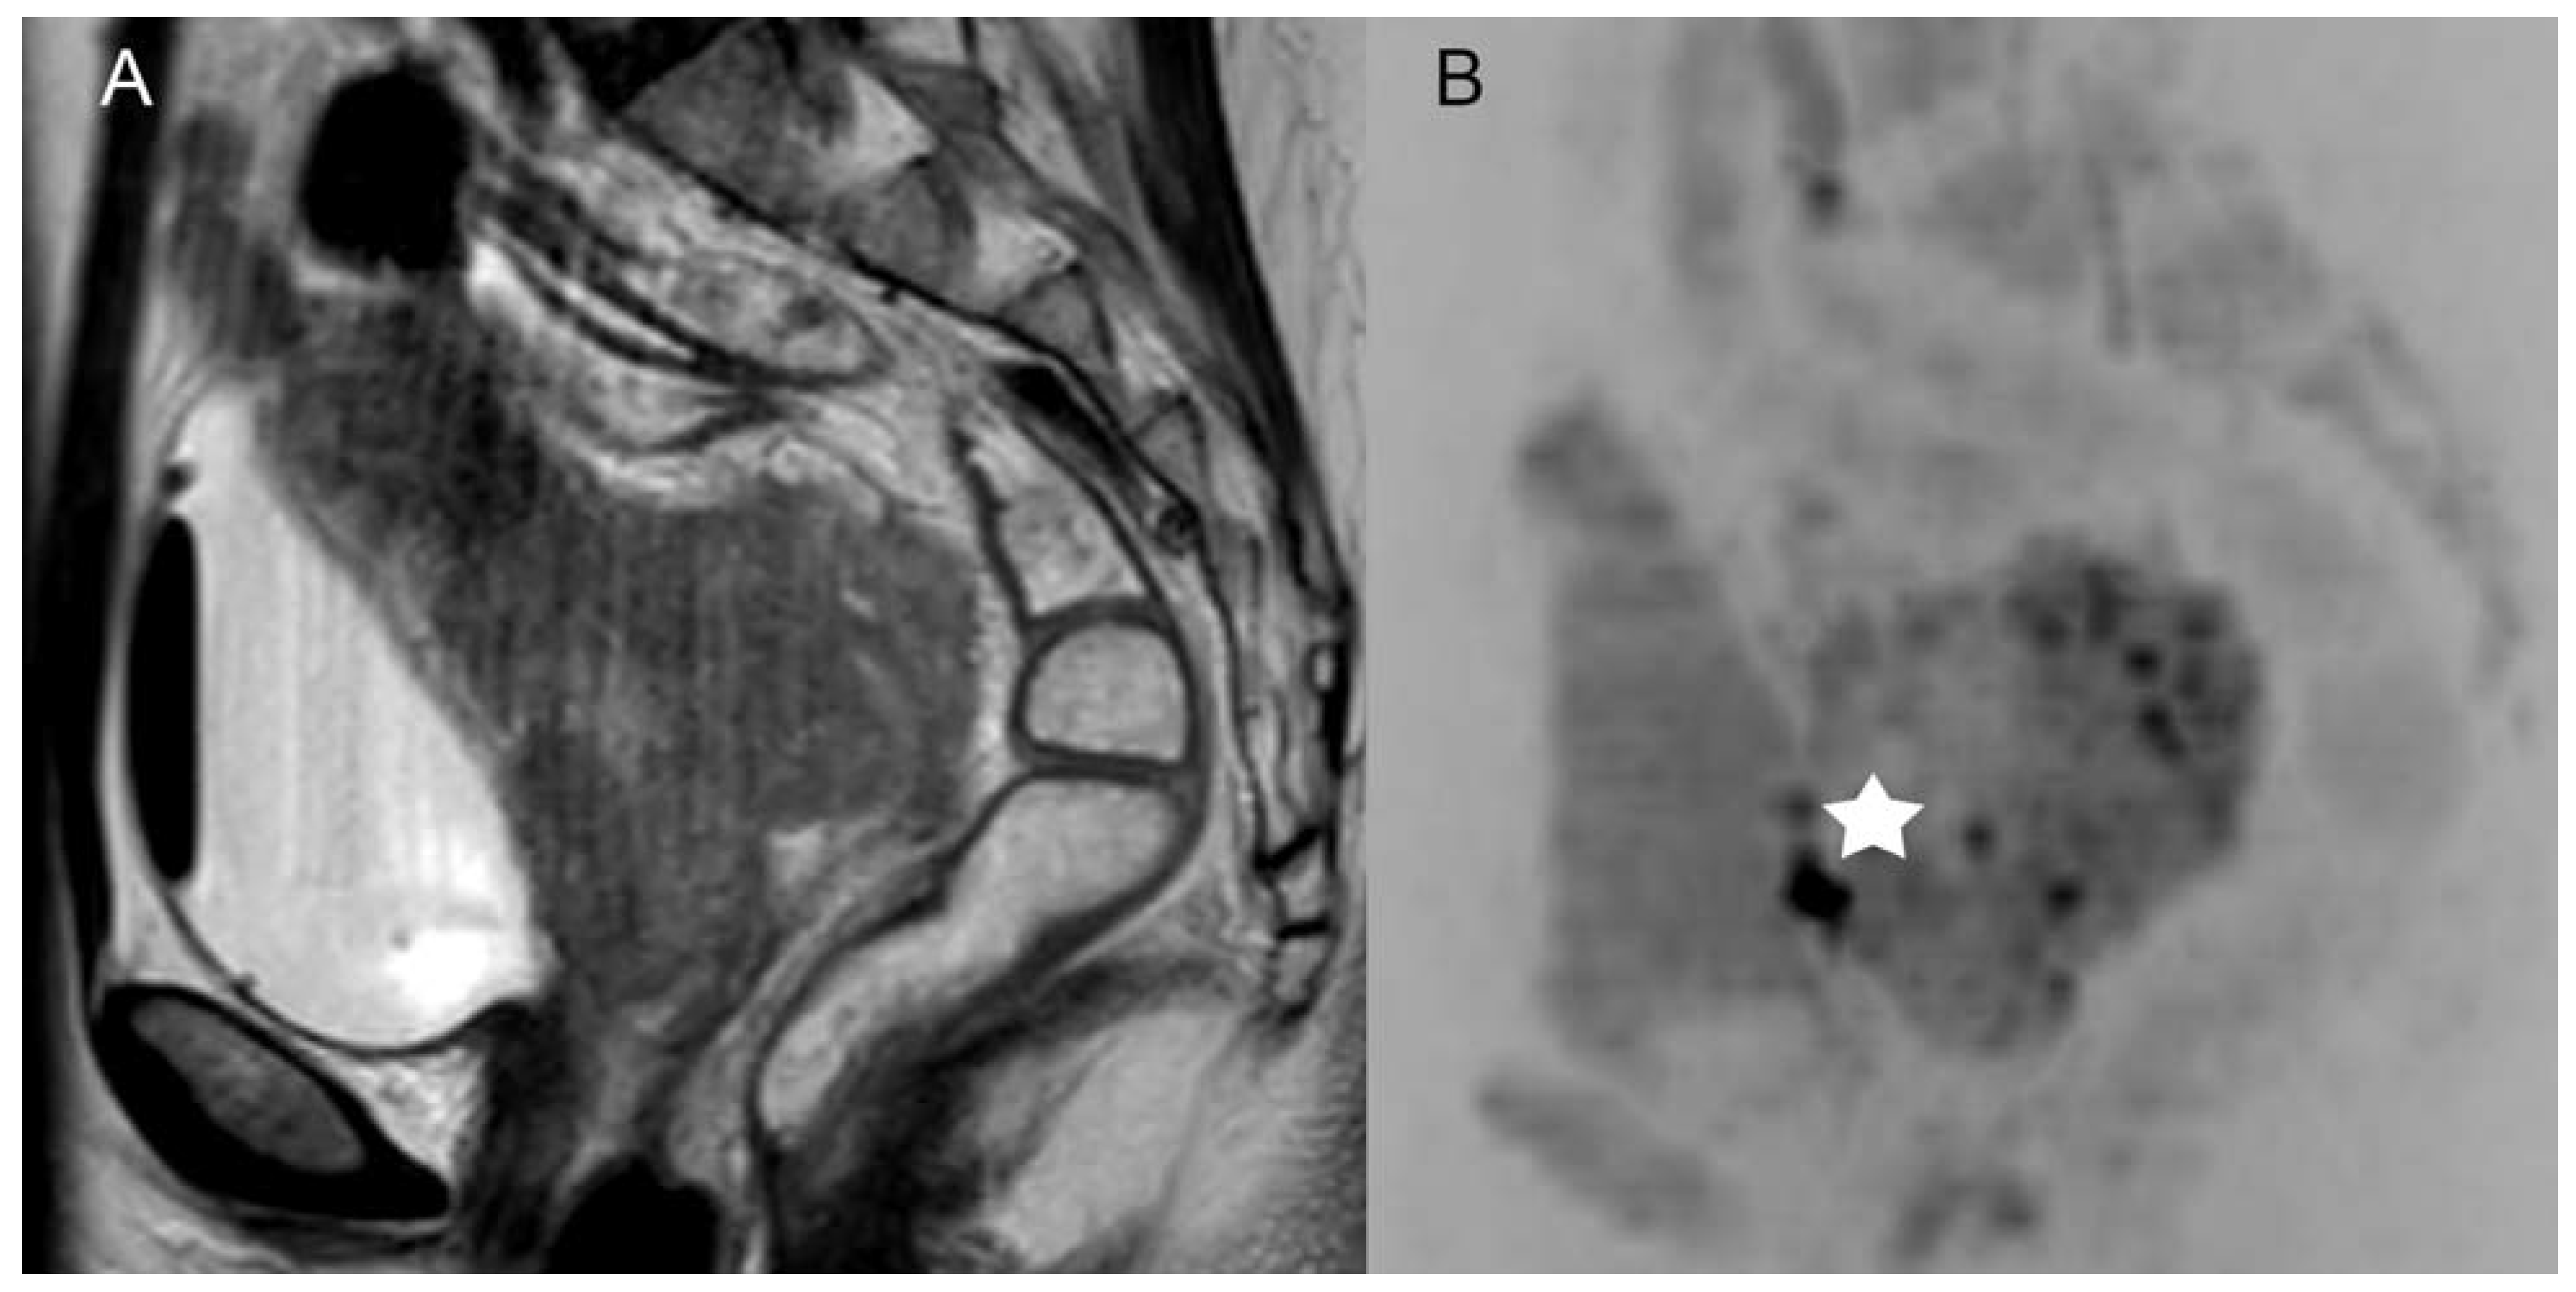

Figure 2. Example of a patient with a FIGO IB1 cervical cancer with a tumor size of 1.9 × 1.5 cm proven by histopathology. Both readers did overestimate the tumor size in the standard MRI ((A), contrast enhanced transversal T1-weighted scans with fat saturation) with 3.45 cm × 1.85 cm, and both readers correctly downsized the tumor regarding DWIBS (B) with a size of 1.75 × 1.35 cm.